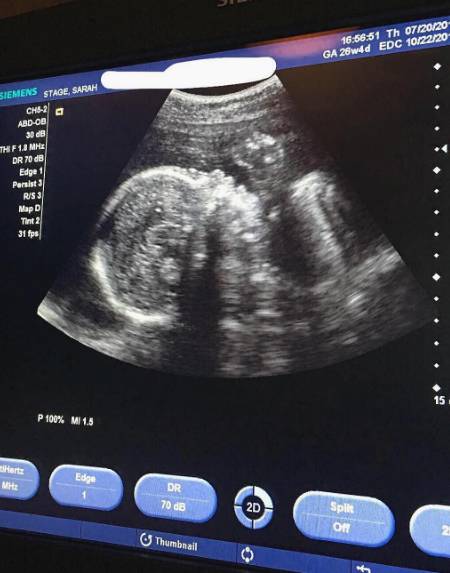

对于网友质疑自己是代孕,Sarah大方地秀出自己产检的B超图,

“小家伙有2斤多啦,医生说宝宝很健康,心跳强健有力!”